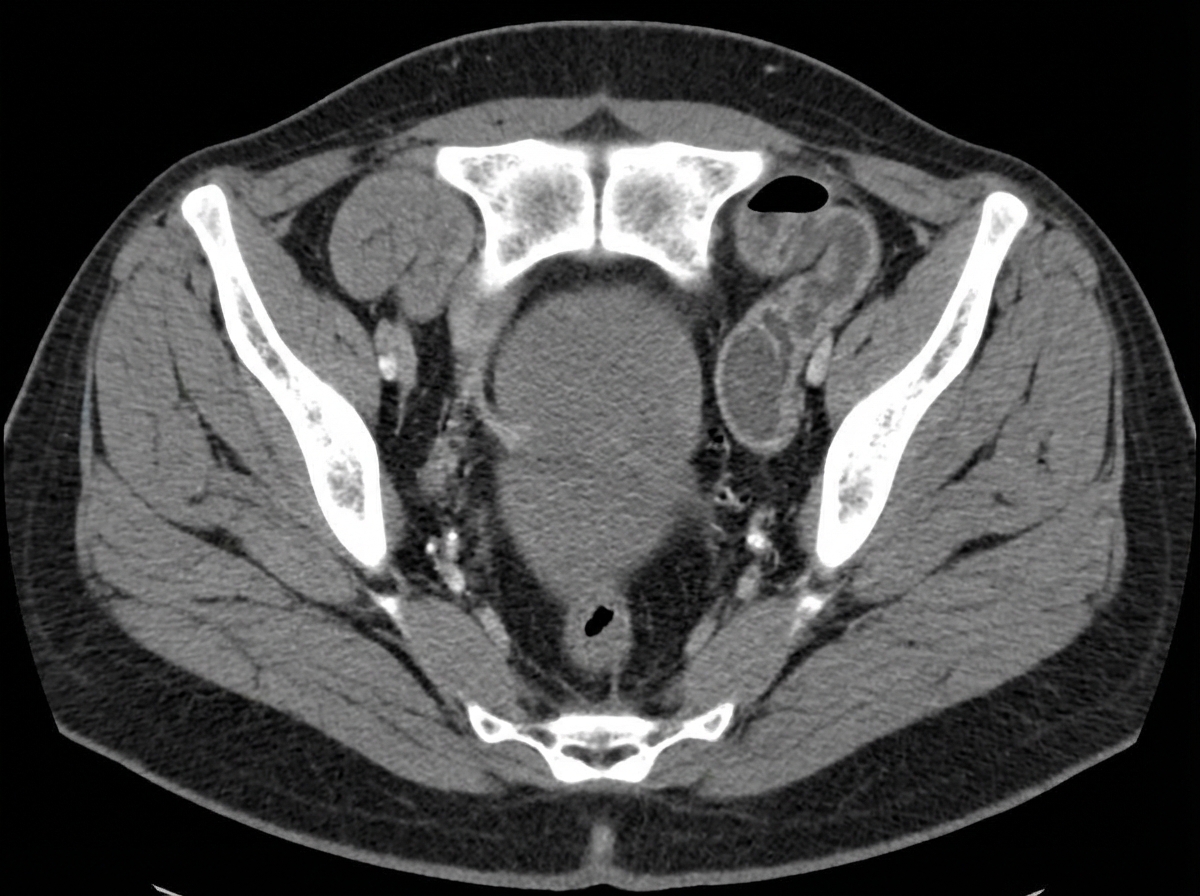

An elderly woman presented with abdominal pain and vomiting for three days. A computed tomogram of the abdomen was obtained. What is the diagnosis?

Explanation: ***Obturator hernia*** - Classic **CT appearance** shows a **bowel loop** herniating through the **obturator foramen** between the **pectineus** and **obturator externus muscles**. - Typically occurs in **elderly, thin women** and can cause **small bowel obstruction** with the characteristic **Howship-Romberg sign** (medial thigh pain). *Cecal volvulus* - CT shows a **dilated cecum** in an abnormal position, often in the **left upper quadrant** with a **whirl sign** at the point of torsion. - Creates a **closed-loop obstruction** with characteristic **coffee bean** or **kidney-shaped** appearance on imaging. *Intussusception* - CT demonstrates the pathognomonic **target sign** or **bowel-within-bowel** appearance with alternating layers of bowel wall. - More commonly seen in **pediatric patients** and would show a **sausage-shaped mass** rather than herniation through anatomical foramina. *Mesenteric ischemia* - CT findings include **bowel wall thickening**, **pneumatosis**, **portal venous gas**, and **lack of bowel wall enhancement** with contrast. - Would show **mesenteric vessel occlusion** or **bowel wall necrosis** rather than mechanical obstruction from herniation.